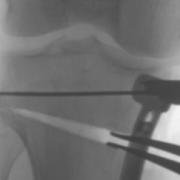

An osteotomy is a surgical procedure to cut and re-align a bone. In an 'opening wedge' osteotomy, laminar spreaders open the wedge in the bone which is held in the new position with a plate and screws until new bone fills the gap. In a closing wedge osteotomy, a wedge of bone is removed and the gap closed and plated.